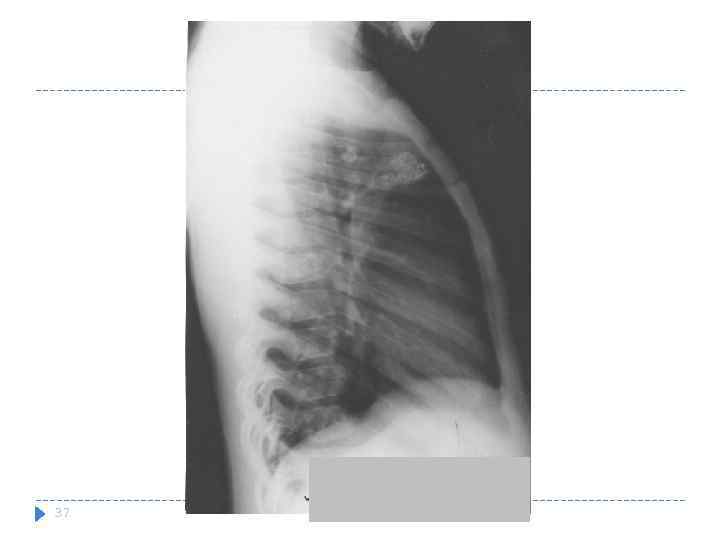

Множественные кальцинаты бронхопульмональной группы справа

Множественные кальцинаты бронхопульмональной группы справа

37

37